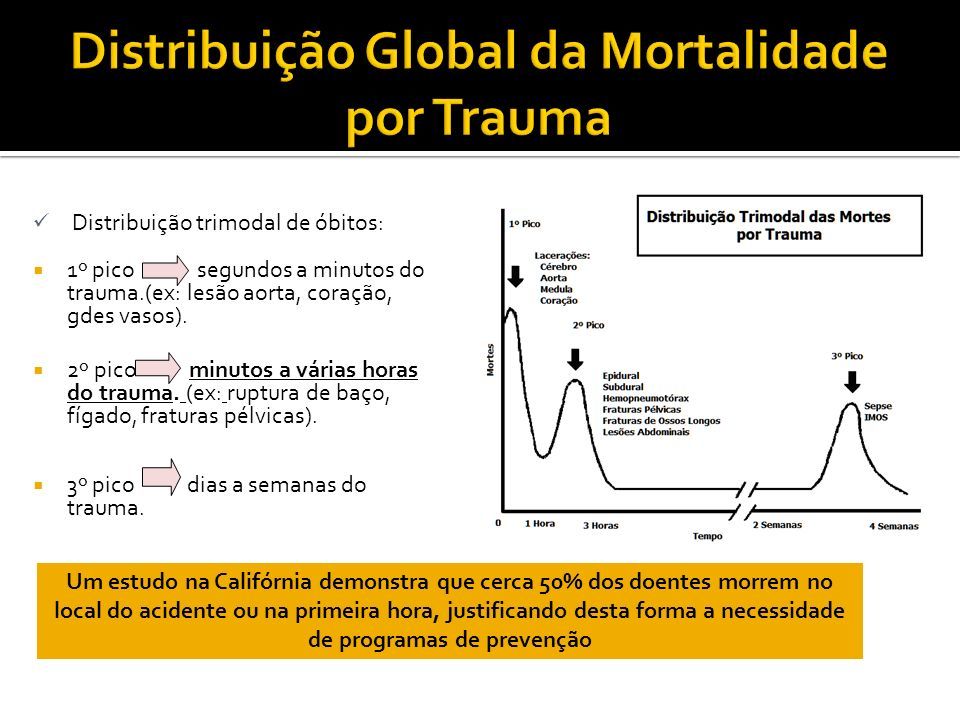

Como acontece a distribuição trimodal do trauma?

Segundos a minutos: prevenção

Minutos a 24 h: ATLS

> 24h: medicina